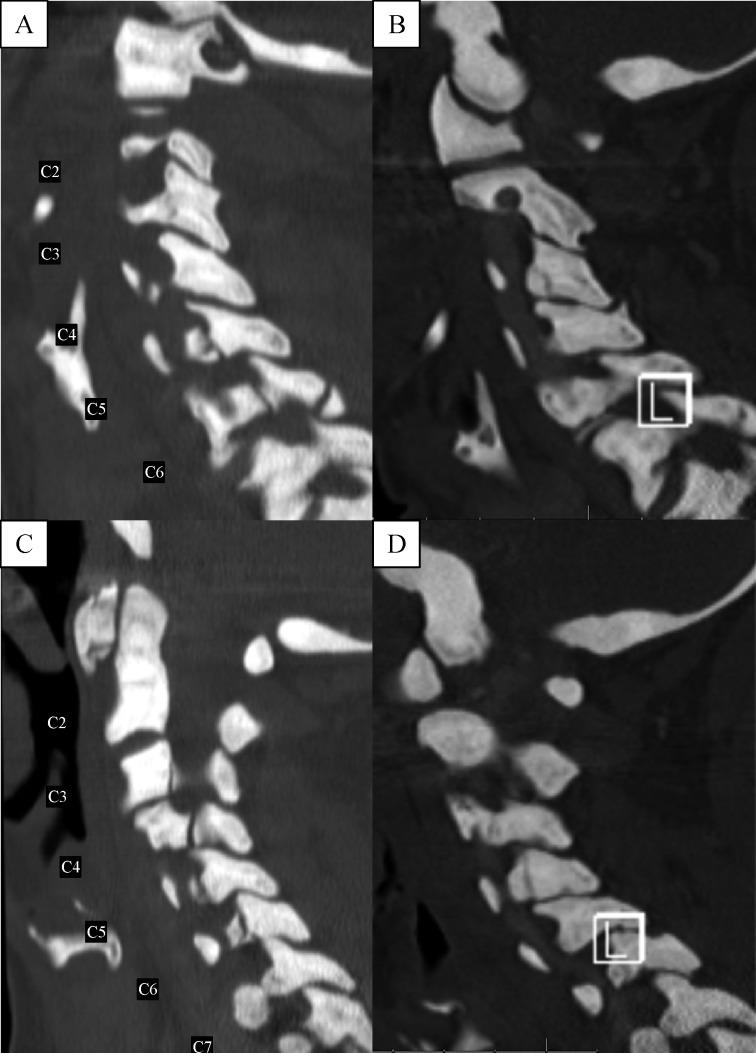

While management of appendicular fractures has been well described in the setting of osteopetrosis, there is limited information on managing fractures of the axial spine. Here we present an osteopetrotic patient with multiple traumatic multiple, comminuted, unstable cervical spinal fractures managed with non-operative stabilization, and provide a review of the pathophysiology, genetic characteristics, and special considerations that must be explored when determining operative versus non-operative management of spinal injury in osteopetrosis. A PubMed query was performed for English articles in the literature published up to June 2016, and used the following search terms alone and in combination: "osteopetrosis", "spine", "fractures", "osteoclasts", and "operative management". Within four months after initial injury, treatment with halo vest allowed for adequate healing. The patient was asymptomatic with cervical spine dynamic radiographs confirming stability at four months. On four-year follow up examination, the patient remained without neck pain, and CT scan demonstrated partially sclerotic fracture lines with appropriate anatomical alignment. In conclusion, external halo stabilization may be an effective option for treatment of multiple unstable acute traumatic cervical spine fractures in patients with osteopetrosis. Given the challenge of surgical stabilization in osteopetrosis, further research is necessary to elucidate the optimal form of treatment in this select patient population.

虽然在骨质石化症背景下,四肢骨折的处理已有详尽描述,但关于轴性脊柱骨折的处理信息有限。在此,我们介绍一名患有多发性创伤性、粉碎性、不稳定型颈椎骨折的骨质石化症患者,其采用非手术固定治疗,并对骨质石化症患者脊柱损伤手术与非手术治疗决策时必须探究的病理生理学、遗传特征及特殊注意事项进行综述。在PubMed上检索截至2016年6月发表的英文文献,单独及组合使用以下检索词:“骨质石化症”“脊柱”“骨折”“破骨细胞”及“手术治疗”。初次损伤后4个月内,采用头环背心治疗实现了充分愈合。患者无症状,颈椎动态X线片证实4个月时稳定。在4年随访检查中,患者无颈部疼痛,CT扫描显示骨折线部分硬化,解剖对位良好。总之,对于骨质石化症患者的多发性不稳定急性创伤性颈椎骨折,外固定头环可能是一种有效的治疗选择。鉴于骨质石化症手术固定的挑战,有必要进一步研究以阐明这一特定患者群体的最佳治疗方式。